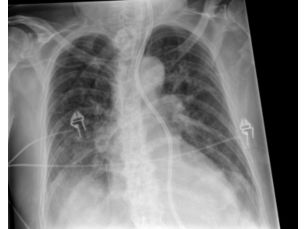

La Radiografia De Torax En La Unidad De Cuidados Intensivos Imagen Diagnostica

Coronavirus Los Rayos X Muestran La Forma En Que La Infeccion Por Covid 19 Destruye Los Pulmones Observatorio Regional De Tuberculosis De Las Americas

Los Radiologos Muestran Imagenes De Lo Que Hace El Coronavirus En Los Pulmones

Hallazgos Radiologicos De 81 Pacientes Con Neumonia Por Covid 19 En Wuhan Covid 19 Intramed